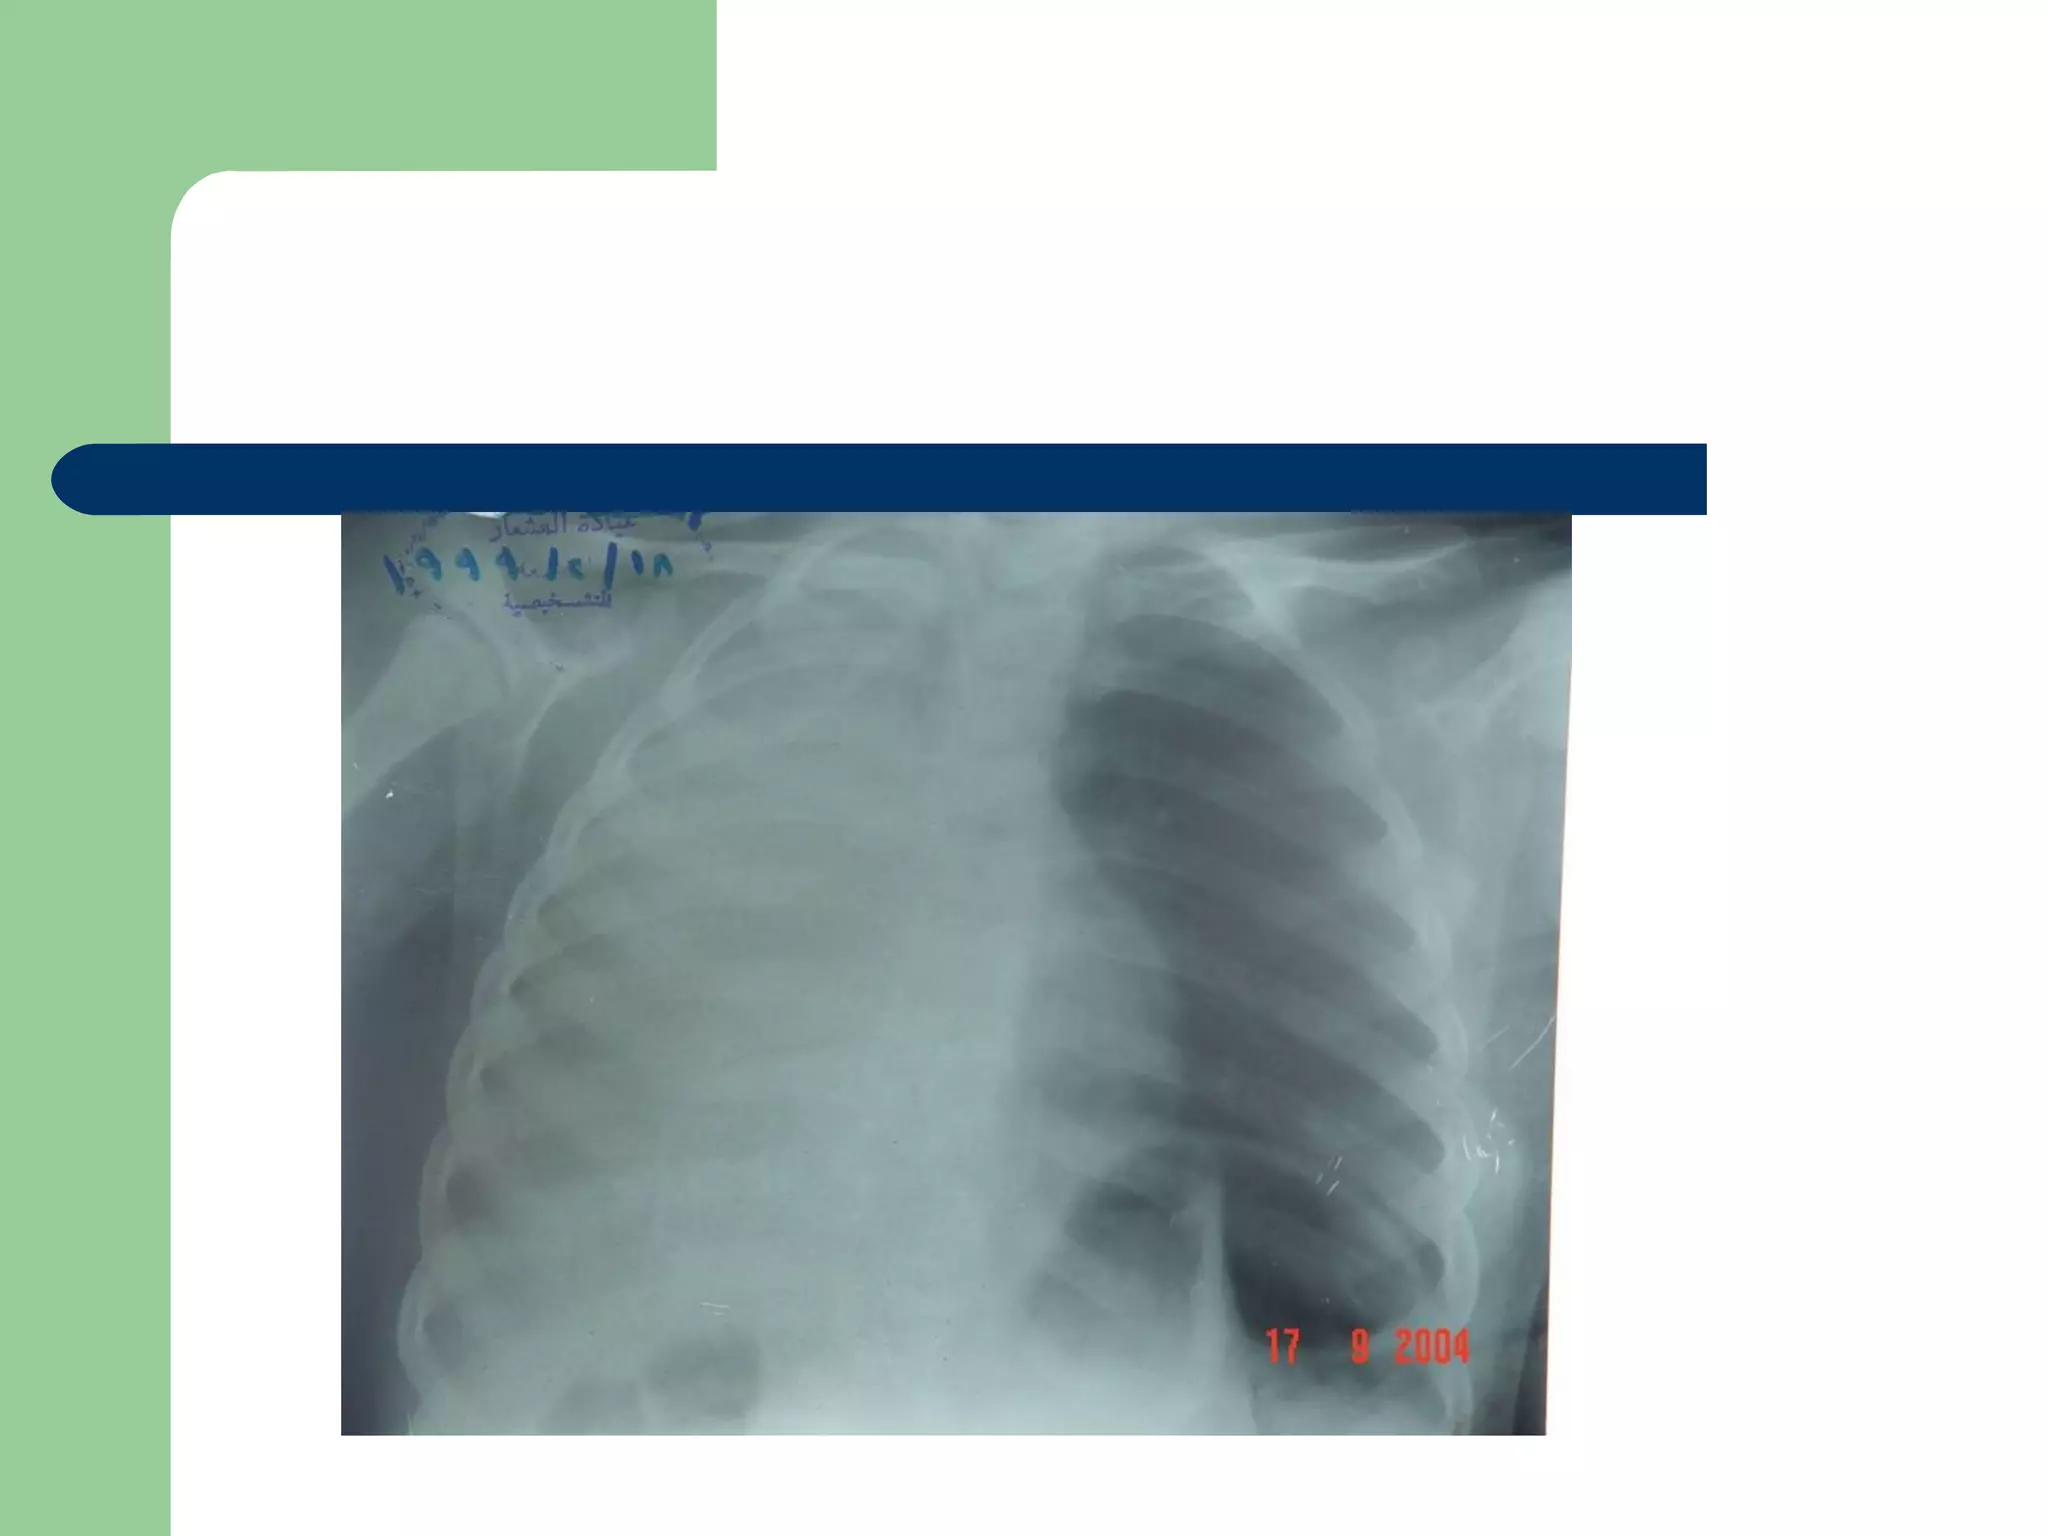

A five and a half yr old boy: non-resolved cough

Of 40 days duration

DIAGNOSIS…  Examination:signs of respiratory distress may be present.  CXR may be normal if the FB is not radio- opaque. or it can show a radio- opaque FB such as bone. Obstructive emphysema: is produced by intra-bronchial FB that allows air to enter in inspiration and prevents its exit in expiration. Lung collapse (complete or partial) is produced by a FB that blocks the bronchus completely. Unresolved pneumonic consolidation. Lung abscess or broncheictasis are caused by a long-standing FB.

A five anda half yr old boy: non-resolved cough Of 40 days duration